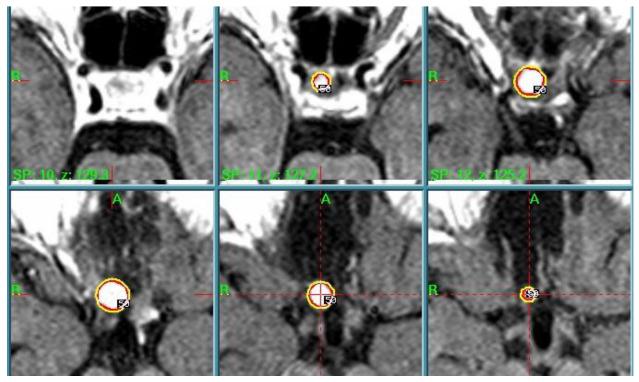

伽玛刀手术在罕见鞍区肿瘤治疗中的作用:9例报告

The Role of Gamma Knife Surgery in the Treatment of Rare Sellar Neoplasms: A Report of Nine Cases.

The group of so-called "sellar-region masses" consists of a heterogeneous group of neoplasms and tumor-mimicking lesions, whose differential diagnosis may be challenging due to the overlapping of clinical and radiological features, which can be found both in "common" and "uncommon" lesions. The choice of a correct treatment strategy is still arduous and requires histological analysis. Gamma Knife Radiosurgery (GKRS) has already been reported as a safe and effective treatment in these cases. The objective of this study is to evaluate single-center pre-operative data, post-operative outcomes, and long-term follow-up in patients treated with GKRS for unusual sellar tumors. We retrospectively identified and analyzed nine patients treated with GKRS from 2004 to 2015, according to a standard protocol. Lesions consist of hypothalamic hamartoma (HH), Rathke's cleft cist (RCC), Langerhans cell histiocytosis (LCH), spindle cell oncocytoma (SCO), choroid plexus papilloma (CPP), and ossifying fibroma (OF). The diagnosis was histologically confirmed in six patients that underwent surgery, while in three patients, diagnosis was based on characteristic clinical and radiological findings (two HH and one RCC). Pre-operative and post-operative data were retrieved from medical archives, and long-term follow-up was obtained through clinical and neuroradiological periodic examination. In our series, all the "rare" sellar lesions treated, had a successful radiographic and clinical response in a medium-long follow-up period. The long-term follow-up results suggest that GKRS is a safe and effective treatment in rare sellar lesions, with very low toxicity. To the best of our knowledge, this report represents the largest series of unusual sellar lesions treated with GKRS in a single high-volume center, suggesting that GKRS might be an effective non-invasive adjuvant treatment option. Further studies and a larger number of patients are needed to confirm if residuals of these rare sellar lesions might regress on their own without treatment or if other non-invasive treatments could be as effective as GKRS.

摘要